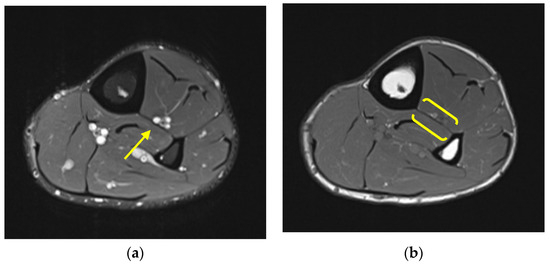

Case 1: A 22-year-old male professional basketball player presented with right leg pain after running into a camera man during a game. He experienced immediate leg pain and swelling. He had no prior history of trauma to this area. Physical exam revealed ecchymosis and swelling about the anteromedial aspect of the tibial midshaft with tenderness to palpation. Radiography was unremarkable. MRI revealed a focal tear of the tibiofibular IOM at the level of the mid tibia (Figure 1). No concurrent ligamentous or osseous injury was identified.

Figure 1. Case 1. Axial proton density fat-saturated MR image from a 22-year-old man with focal tear of the tibiofibular IOM at the level of the mid tibia (yellow arrow).